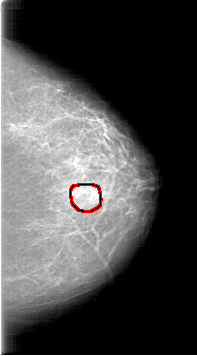

FILE: D_4189_1.LEFT_MLO.OVERLAY

TOTAL_ABNORMALITIES 1

ABNORMALITY 1

LESION_TYPE CALCIFICATION TYPE AMORPHOUS DISTRIBUTION CLUSTERED

ASSESSMENT 0

SUBTLETY 2

PATHOLOGY MALIGNANT

TOTAL_OUTLINES 1

BOUNDARY